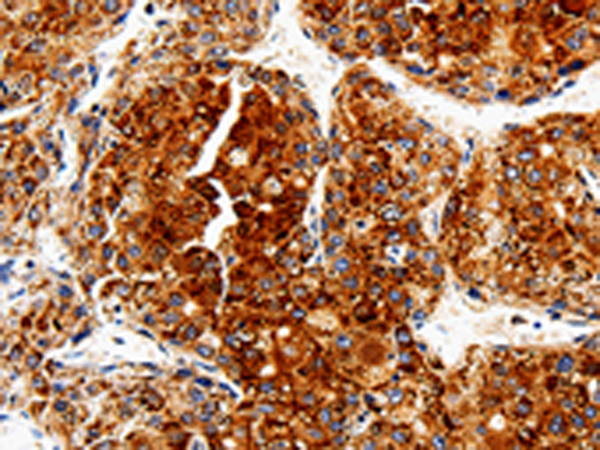

分类: 科研抗体货号: P00095别名: DWFC; JV5-1; MADH5应用: WB,IHC反应种属: Human, Mouse, Rat